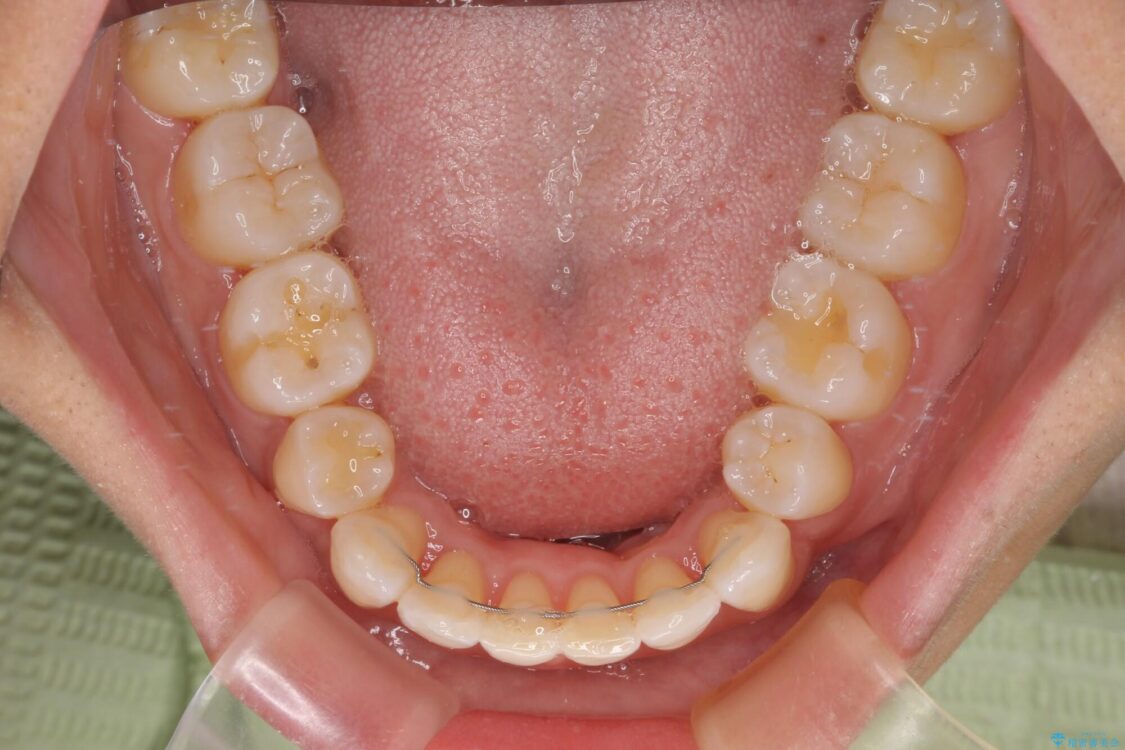

治療前

• 抜歯矯正で唇を閉じやすく 目立たないワイヤー装置 治療前画像